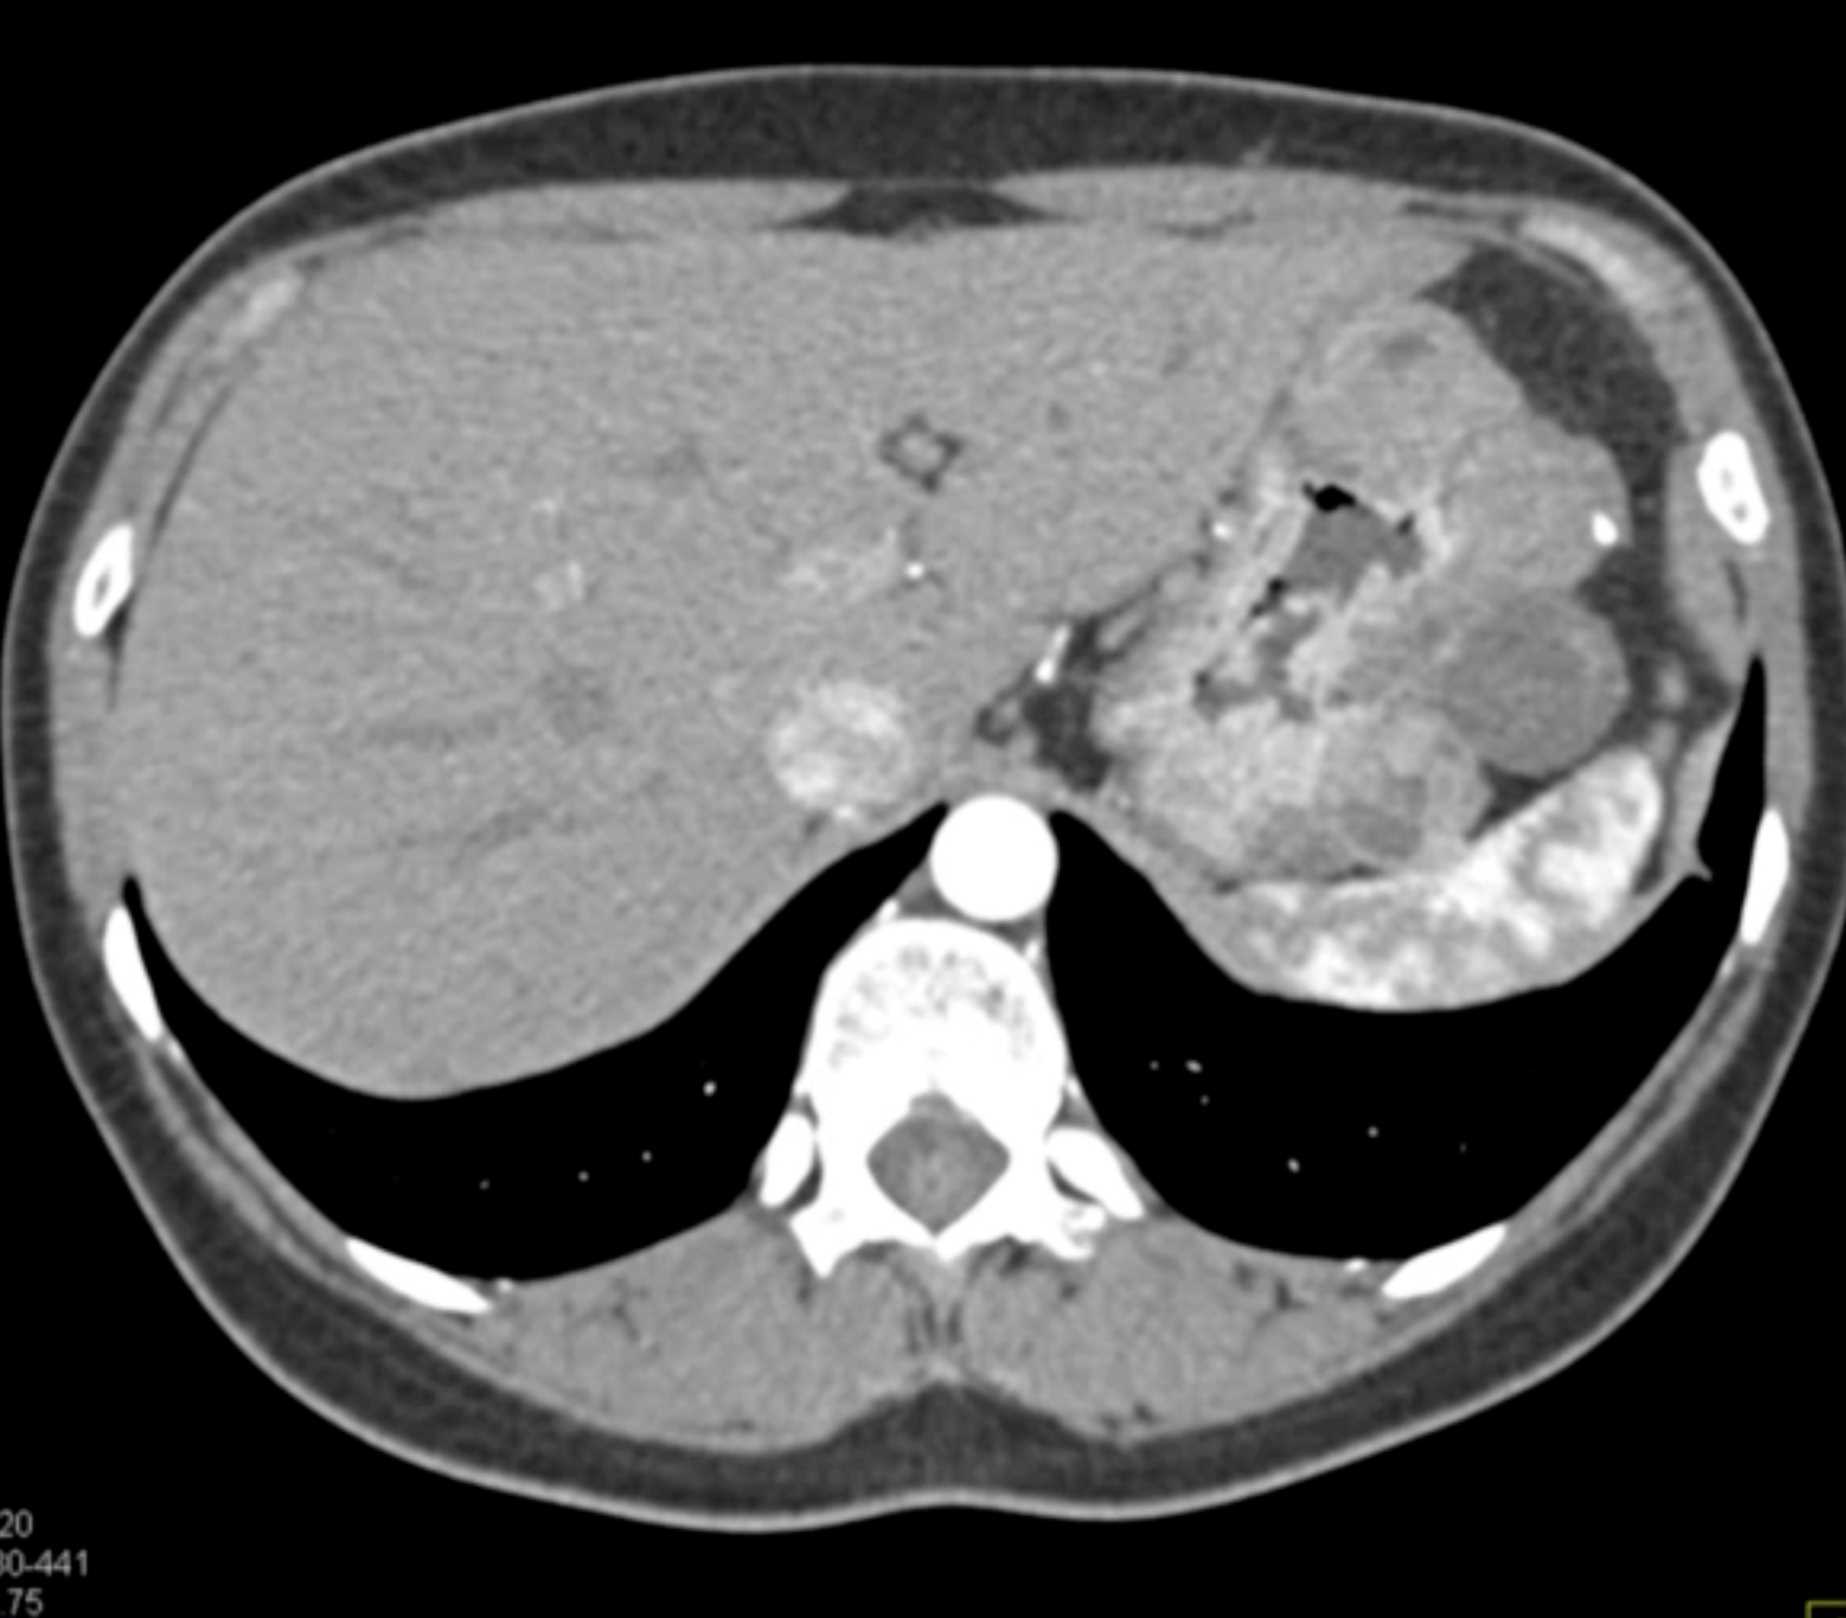

Lagre Gastric GIST Tumor